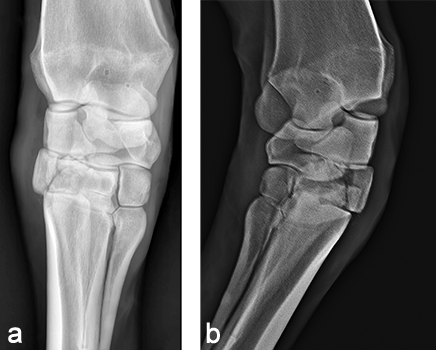

A 4-year-old French warmblood broodmare weighing 570 kg presented with a 5-day history of severe right forelimb lameness following an unwitnessed paddock accident. The limb had been stabilized in a Robert-Jones bandage with caudal and lateral splints prior to referral. The radiographs confirmed a slab fracture of the third carpal bone as well as a comminuted biarticular fracture of the fourth carpal bone (Fig 5). An arthrodesis of the carpometacarpal and middle carpal joint was elected.